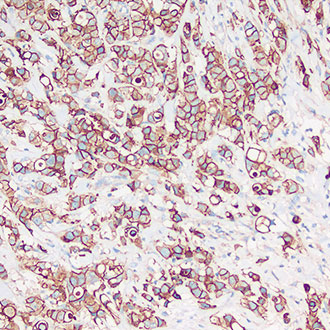

IHC

免疫组织化学(IHC)